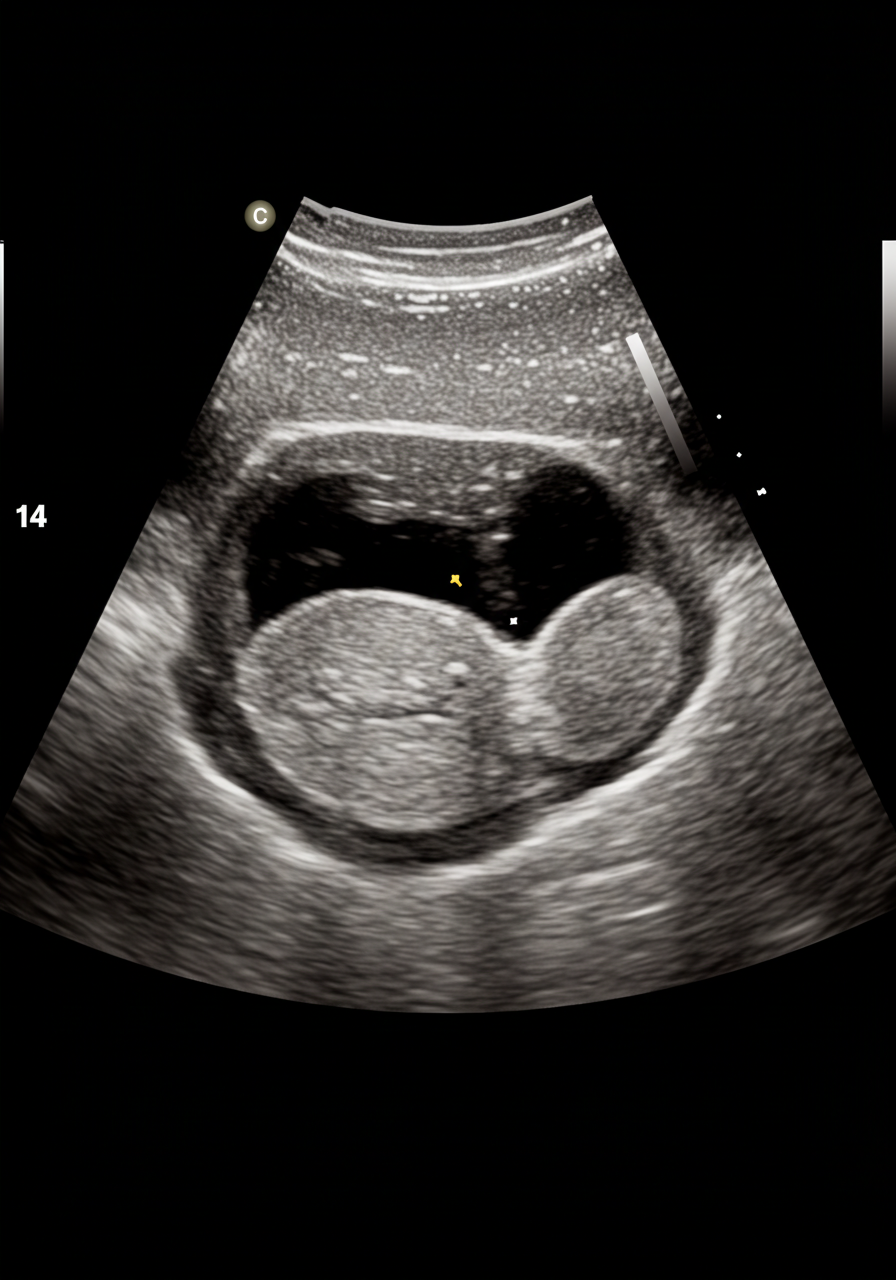

자궁근종의 진단은 주로 초음파 검사를 통해 이루어집니다. 초음파는 자궁의 구조와 크기를 시각적으로 확인할 수 있는 안전하고 비침습적인 방법입니다. 이 검사를 통해 의사는 자궁근종의 위치와 크기를 평가할 수 있습니다.

경우에 따라 MRI(자기공명영상) 검사를 추가로 시행할 수도 있습니다. MRI는 자궁근종의 세밀한 구조를 파악하는 데 유용하며, 다른 질환과의 감별 진단에도 도움을 줍니다. 이러한 진단 방법들은 정확한 진단을 위해 필수적입니다.